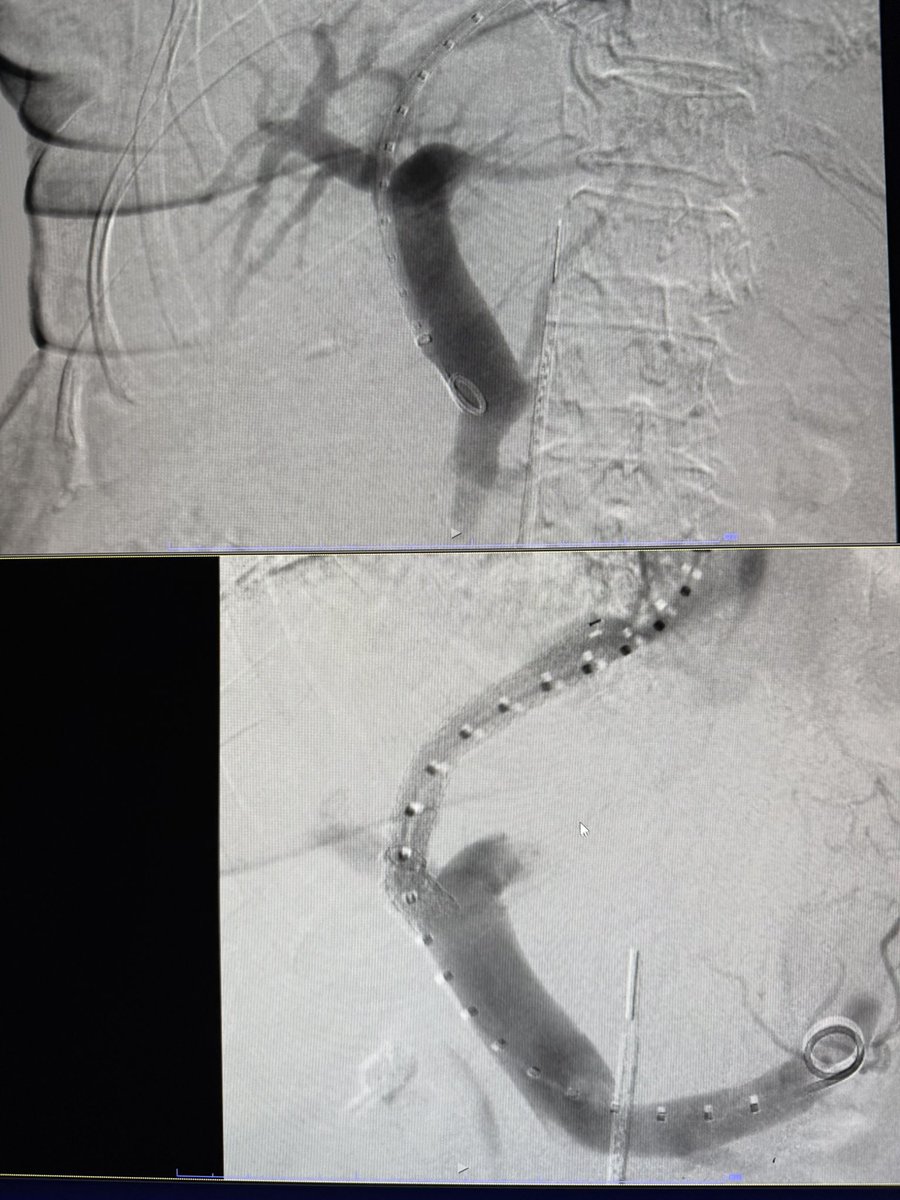

Life saving intervention..looking back 25 some years, couldn’t know in my wildest dreams that I would be able to, but I am fortunate & it has been a privilege to be able to offer it to patients in dire circumstances.

4 TIPS this week, 3/4 with moderate sedation, all under 30 mins to stent deployment. ICE and steerable needles are the future!